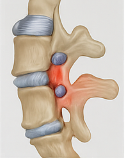

허리디스크(추간판 탈출증)

척추 뼈와 뼈 사이 있는 추간판이 돌출하거나 탈출해 신경을 압박하면 허리통증 원인으로 자주 지목됩니다. 디스크가 밀려 나가면 다리 저림, 감각 이상을 동반하기도 해요. 중년 이후에 특히 주의해야 하는 허리통증 원인이죠.